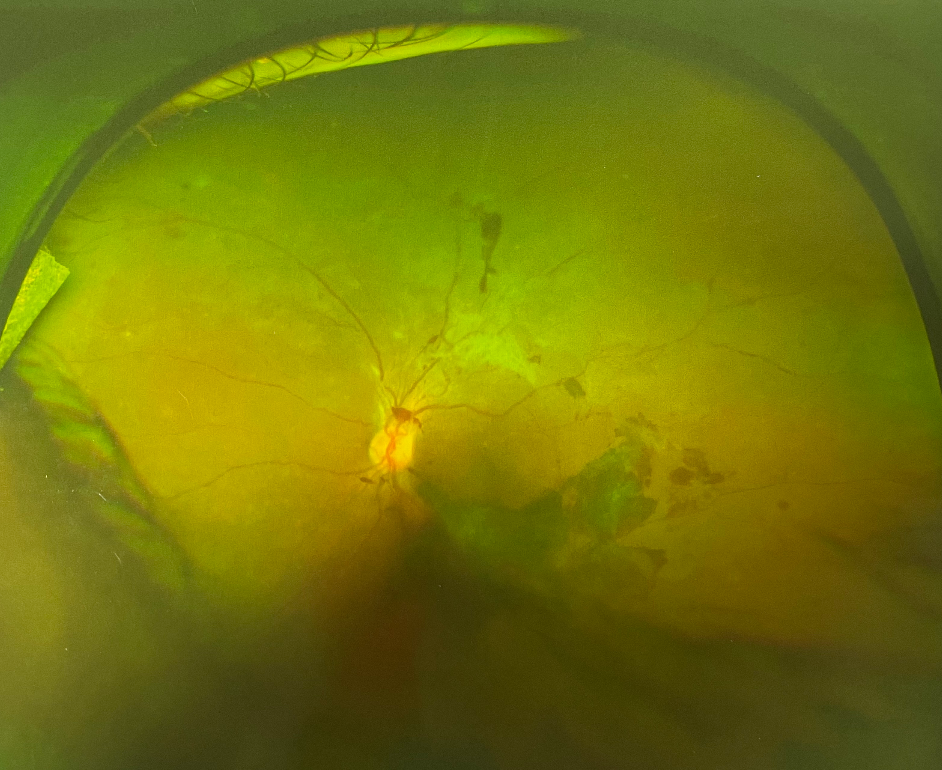

視網(wǎng)膜眼底出血,是眼底血管性病變的一種共同表現(xiàn)。

全身性血管、血液性病變都可以從視網(wǎng)膜及其血管反應(yīng)出來(lái),同時(shí)也可直接引起視網(wǎng)膜出血性病變。

視網(wǎng)膜眼底出血

2、糖尿病視網(wǎng)膜病變

很多糖尿病本人并不知曉,糖網(wǎng)很容易導(dǎo)致眼底出血,而且糖網(wǎng)的眼底出血是逐漸發(fā)展的。

糖網(wǎng)早期僅表現(xiàn)為少量點(diǎn)狀出血,伴微血管瘤,隨病程進(jìn)展可出現(xiàn)點(diǎn)片狀出血和滲出,一旦病變進(jìn)展到增生期或出現(xiàn)黃斑水腫,視網(wǎng)膜新生血管會(huì)導(dǎo)致視網(wǎng)膜前大量出血或玻璃體出血,患者出現(xiàn)視力驟降,嚴(yán)重者幾乎什么都看不見(jiàn)。